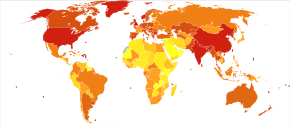

no data

≤110

110–220

220–330

330–440

440–550

550–660

|

660–770

770–880

880–990

990–1100

1100–1350

≥1350

|

COPD usually gets gradually worse over time and can ultimately result in death. It is estimated that 3% of all disability is related to COPD.[125] The proportion of disability from COPD globally has decreased from 1990 to 2010 due to improved indoor air quality primarily in Asia.[125] The overall number of years lived with disability from COPD, however, has increased.[10]